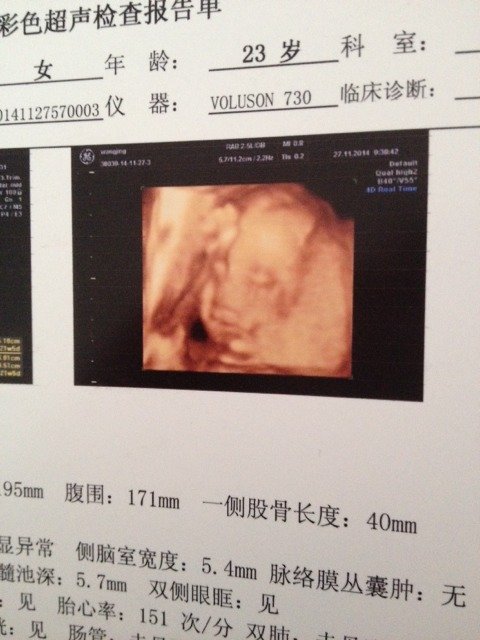

大家帮忙看下我刚刚做的四维彩超 这张图片宝宝是睡着了吗宝宝是睡着了吗 点击展开 静静宝贝 2014-12-11 10:43 为您推荐: 其他回答 你好,这个也不能说明孩子就是睡着了呢,胎儿字母体内这个姿势是很正常的 青丝弯弯月 2014-12-11 17:47 相关问题 今天去做了四维彩超,请问这张图片能看的出宝宝是闺女还是儿子吗?孕25+3那么害羞,呵呵呵 四维彩超有一张图片上面有日期,那个日期是什么意思啊 急!!!请大家帮忙!请有关人士帮我看下这张图片是男宝宝还是女宝宝?